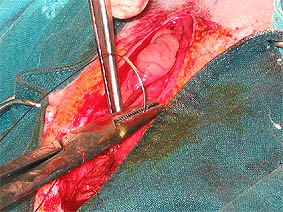

Priprava in fiksacija mehurja za incizijo.

Kirurško odpiranje sečnega mehurja. Pogled na sečne kamne v mehurju.